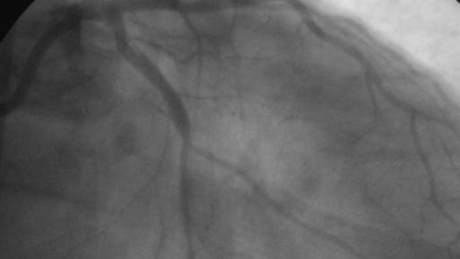

Bild 2: Aufgeblasener Ballon im Verschlussarareal während der Ballondilatation